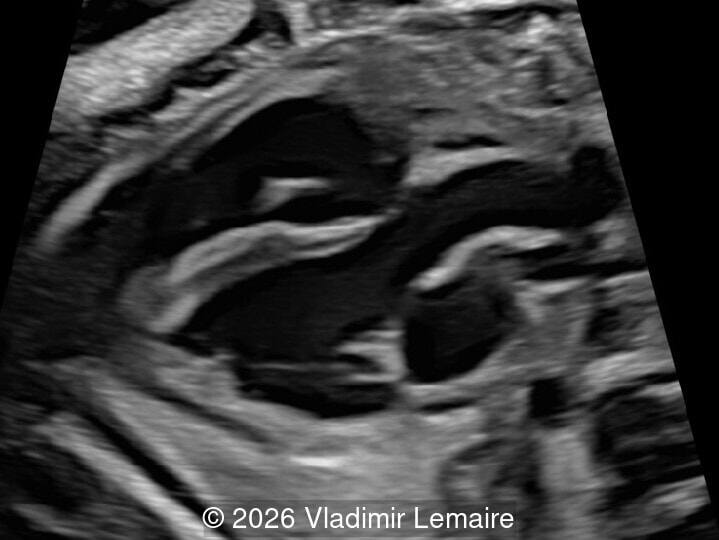

The five-chamber view.

Image 3 The five-chamber view.